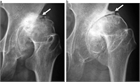

1. 変形性股関節症は進行性の疾患であり、寛骨臼形成不全が強いと病期が進みやすく、関節裂隙狭小化が強いと疼痛が強くなりやすい(エビデンスOJ)。